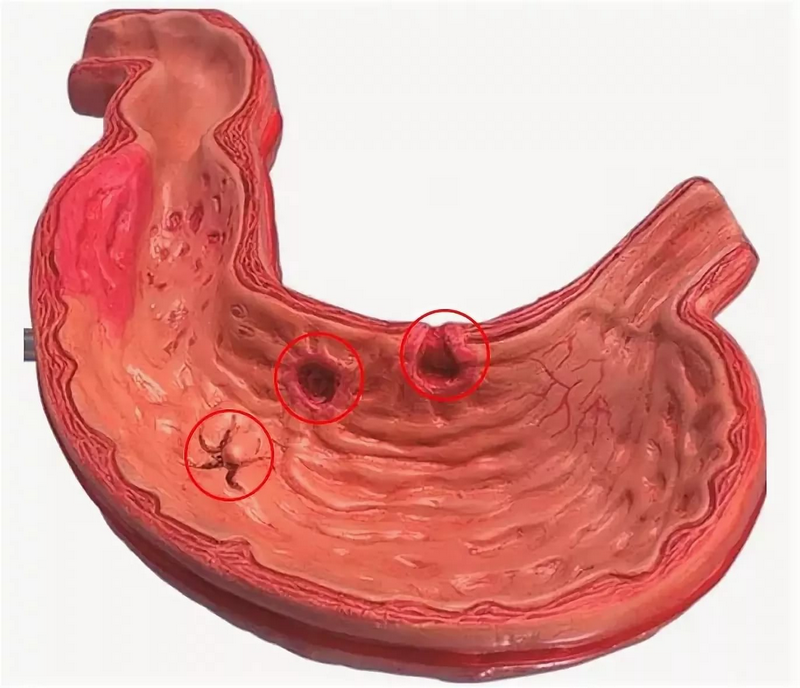

Информация и фотографии о хроническом гастрите и дуодените

Раздел: Фотодневник открытий